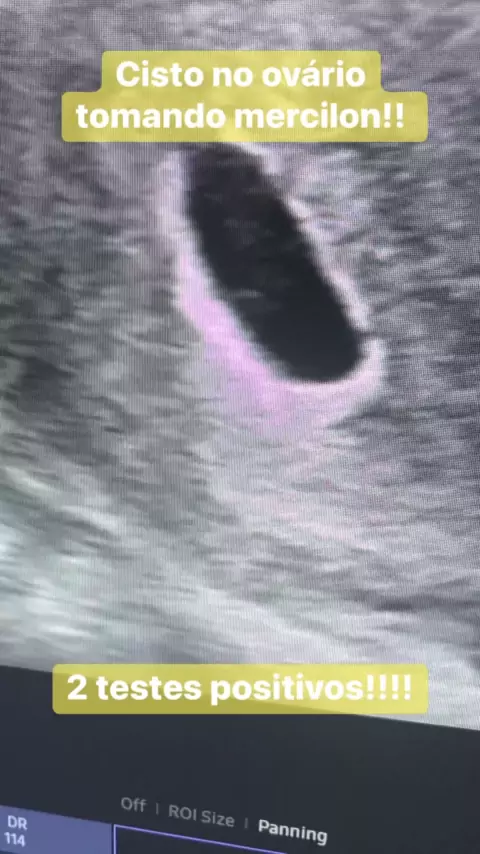

Essa moça estava c cisto no ovário e tomando mercilon!! Porem 2 teste deram positivo! Vdja o q aconteceu